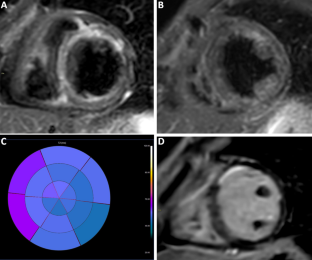

Fig. 2